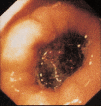

Fig. 1. Imagen endoscópica de cálculo biliar en bulbo duodenal.